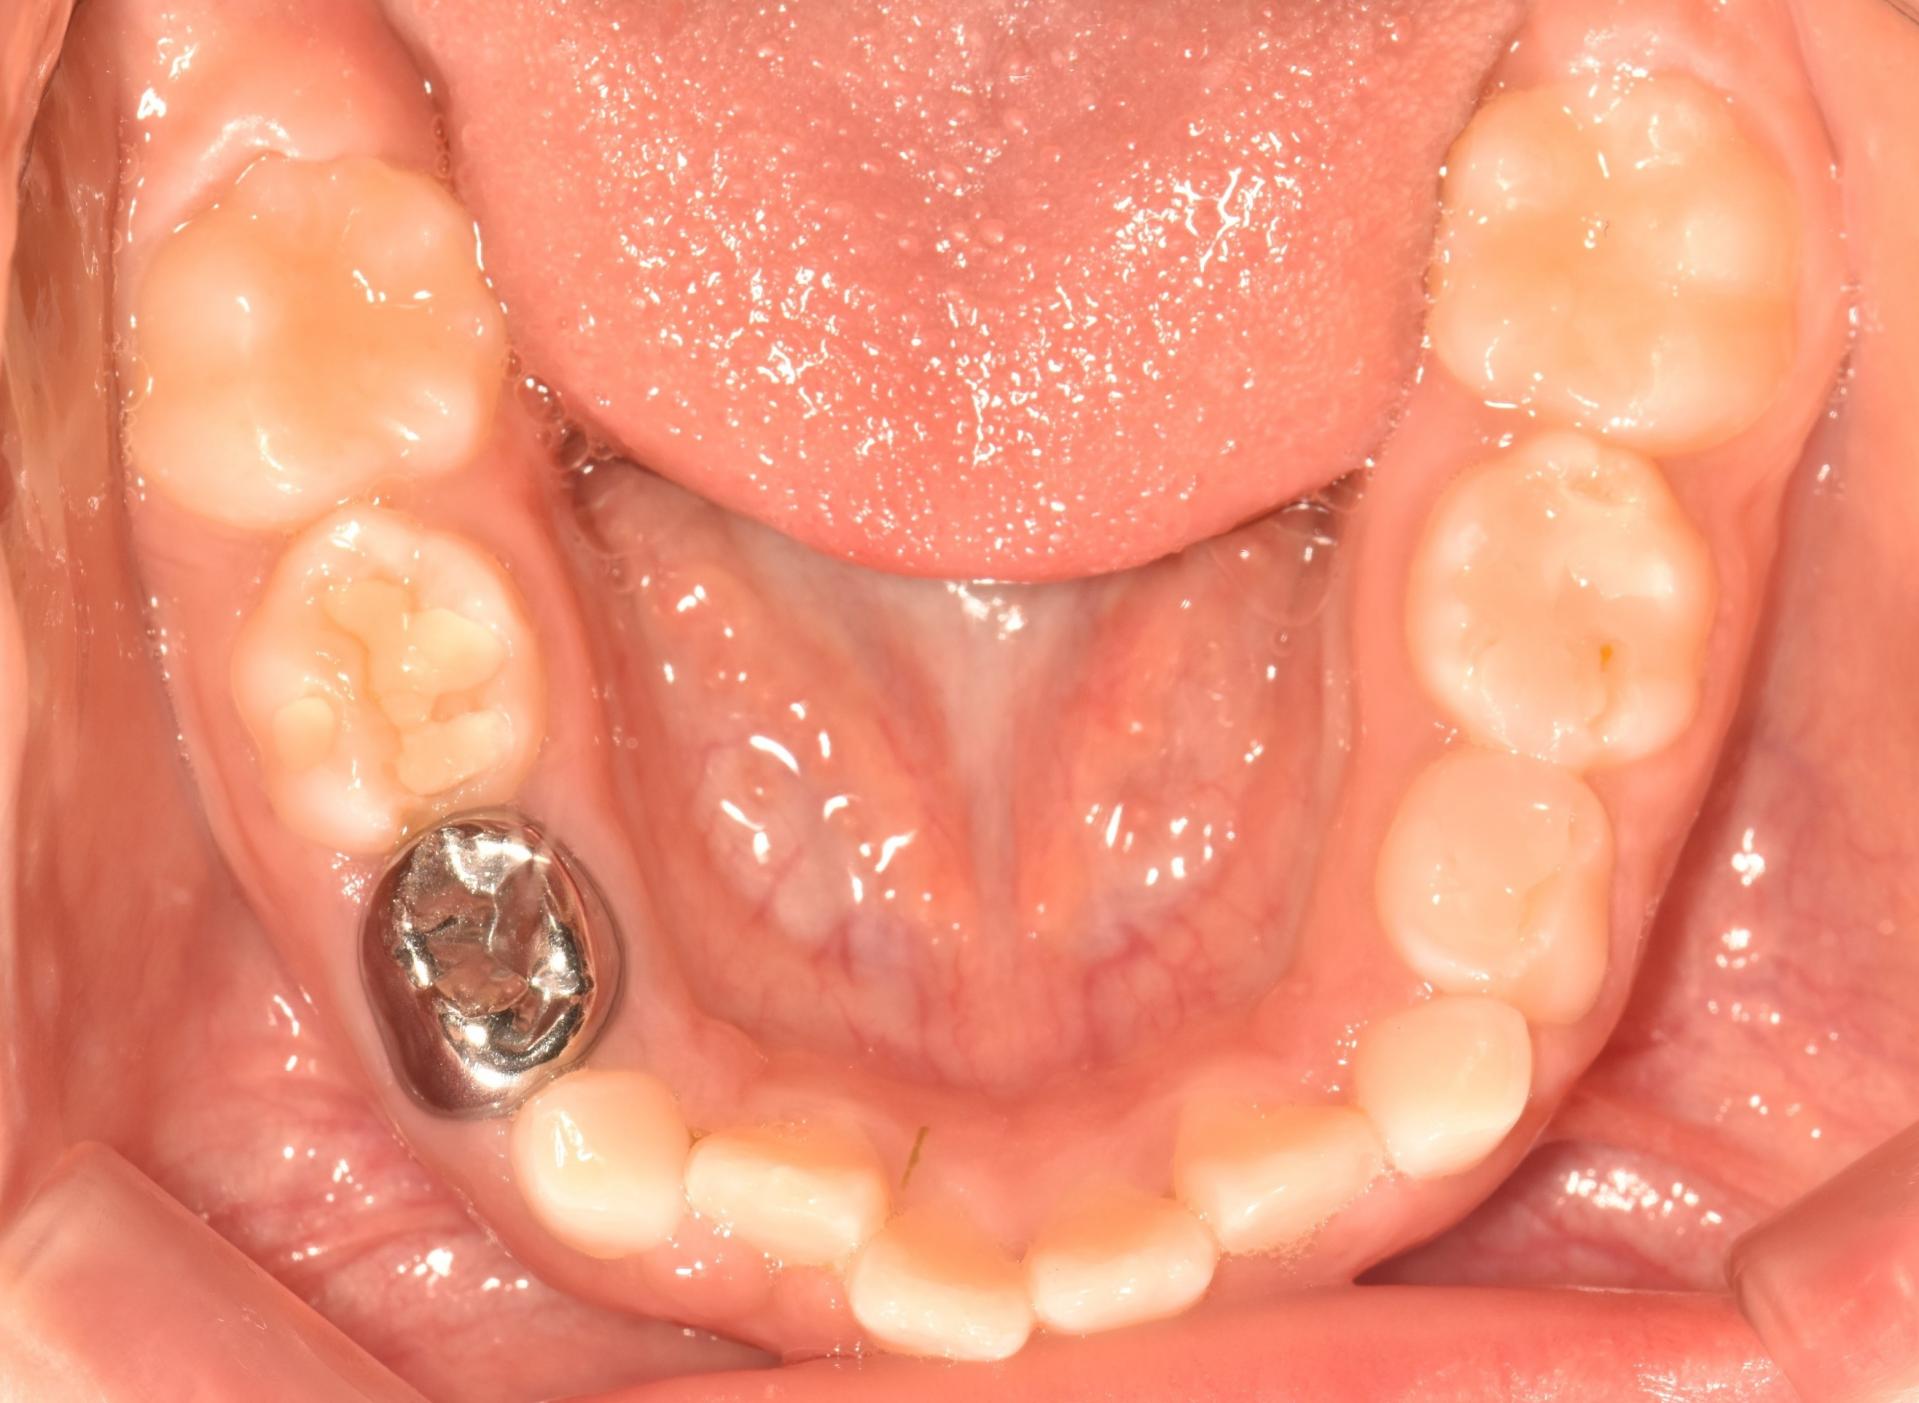

초진입니다. 위아래 앞나의 공간부족으로 이가 삐뚤뺴뚤 나고있고, 앞니도 뻐드려져있네요.